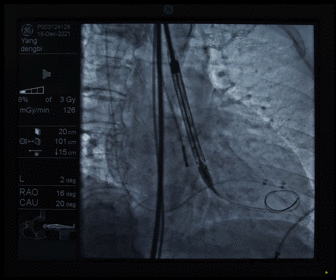

瓣膜释放

造影观察瓣膜形态

术后造影及超声探查未见瓣周漏,跨瓣压差术前47mmHg,术后几乎无压差,术中及术后未出现相关并发症,手术圆满完成。